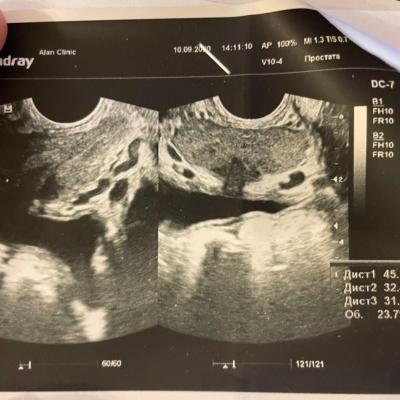

Левофлоксацин 500мг 10 таблеток

Все принимал, попутно сдав анализы на кровь, мочу и сделал ТРУЗИ (Приложил картинками). Уретра все это время остаётся опухшей, плюс я не знал, что мне нужно принимать пребиотики и у меня 4 дня в этом курсе была диарея, да ещё и под индометацином, который драл меня изнутри.

Я пришел меня посмотрели и посмотрели простату, взял сок и сказали по анализам, что "Нет у меня простатита". (Анализы в картинках). Все картинки будут идти по очереди и назначили курс лечения "Неспецифического уретрита". (картинка лечения прикреплена).